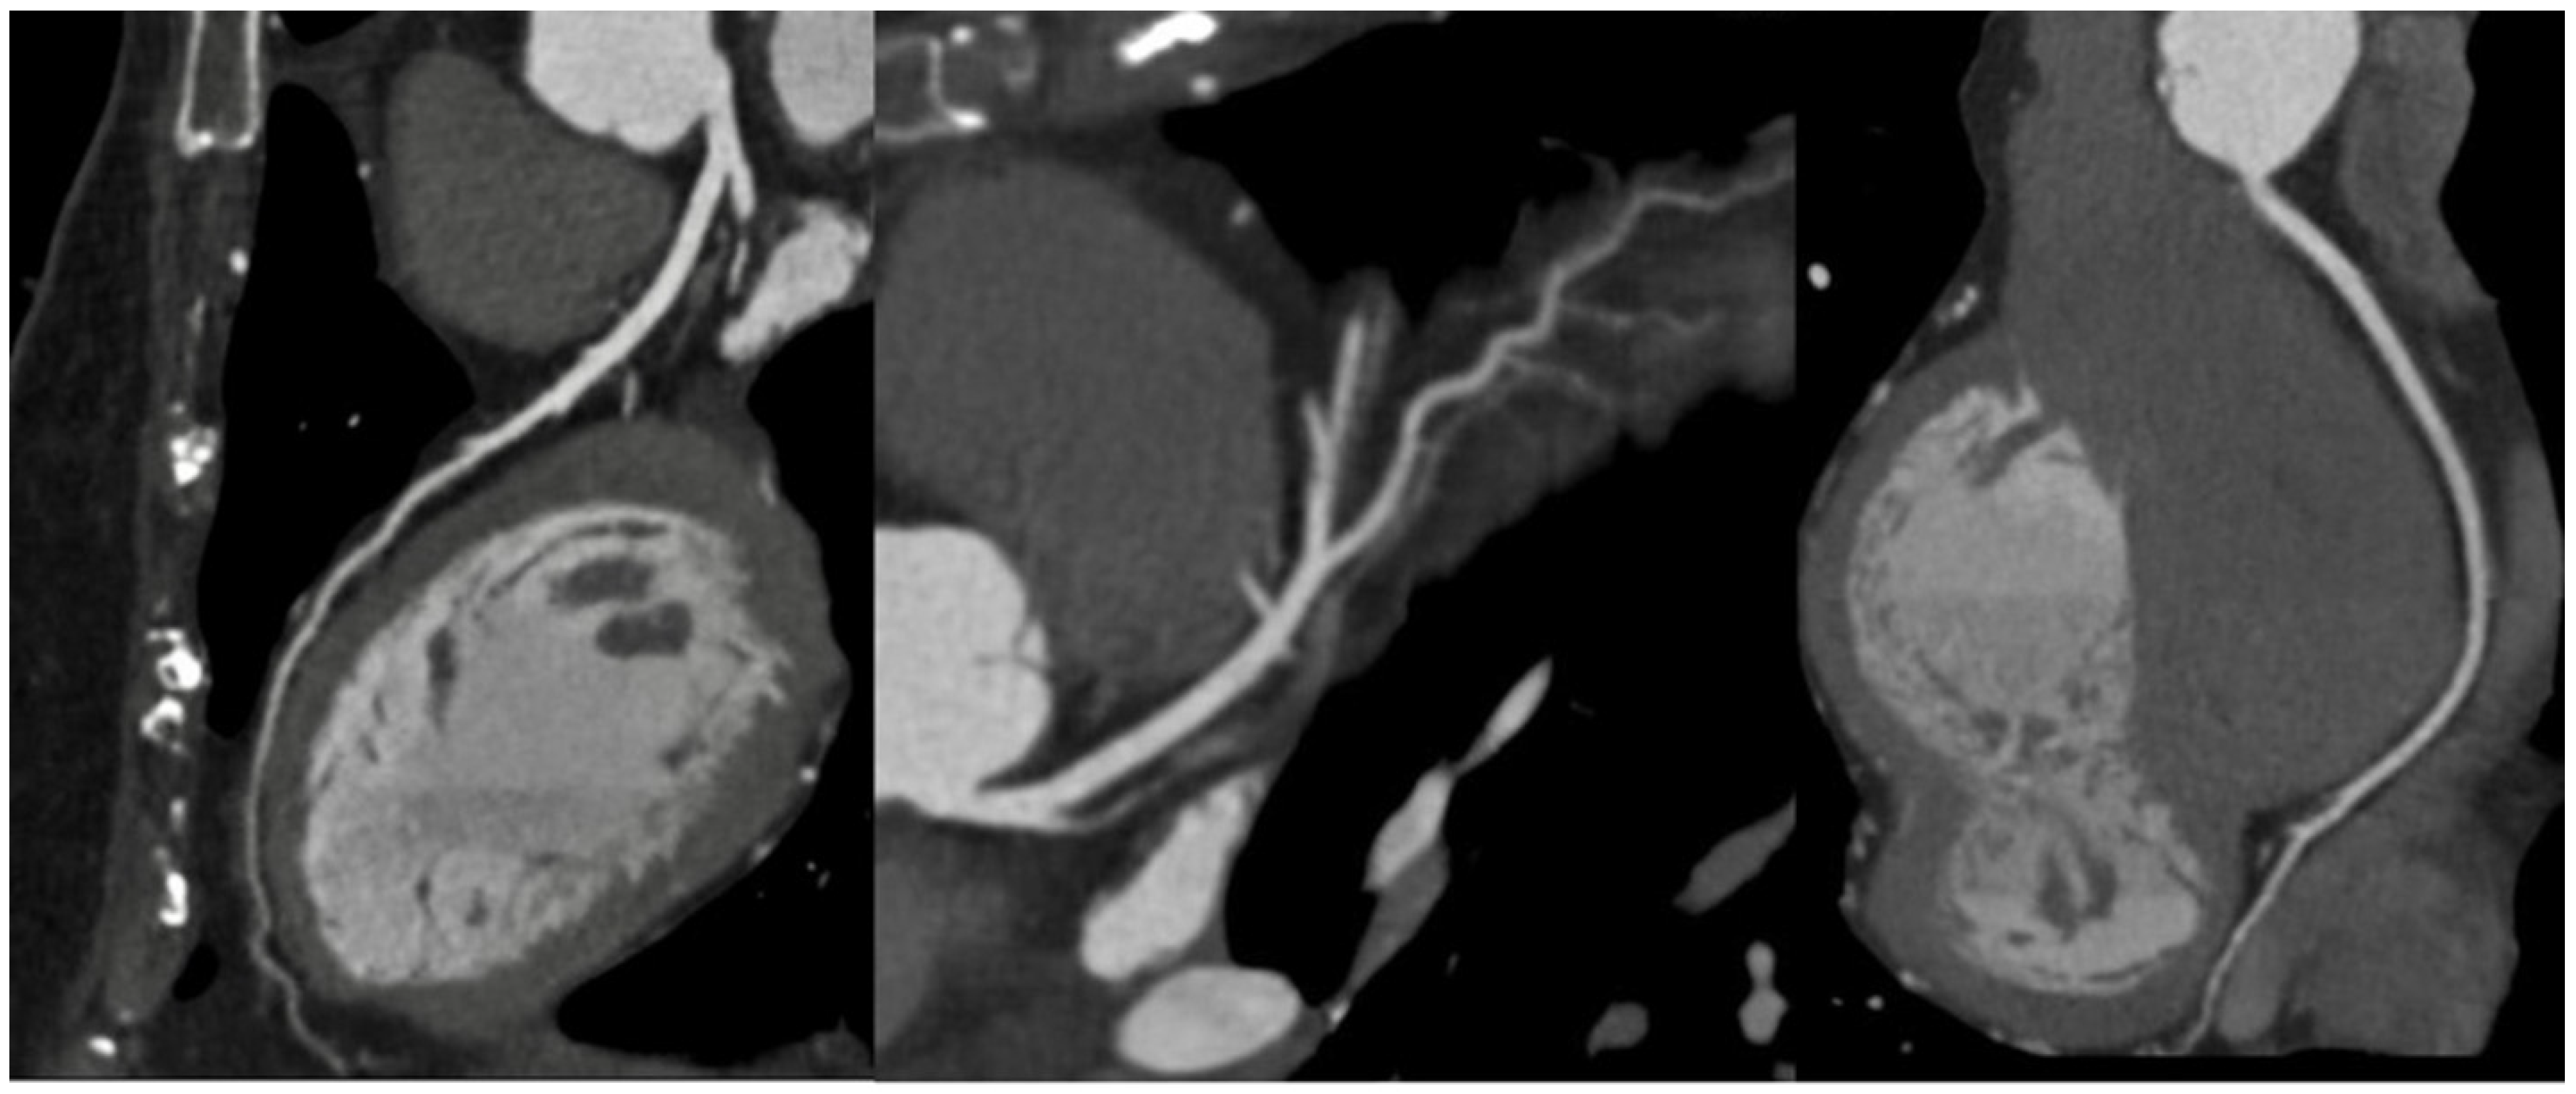

1.1. Computed Tomography

2. Vascular Imaging

- Francone, M.; Budde, R.P.J.; Bremerich, J.; Dacher, J.N.; Loewe, C.; Wolf, F.; Natale, L.; Pontone, G.; Redheuil, A.; Vliegenthart, R.; et al. CT and MR imaging prior to transcatheter aortic valve implantation: Standardisation of scanning protocols, measurements and reporting—A consensus document by the European Society of Cardiovascular Radiology (ESCR). Eur. Radiol. 2020, 30, 2627–2650. [Google Scholar] [CrossRef]